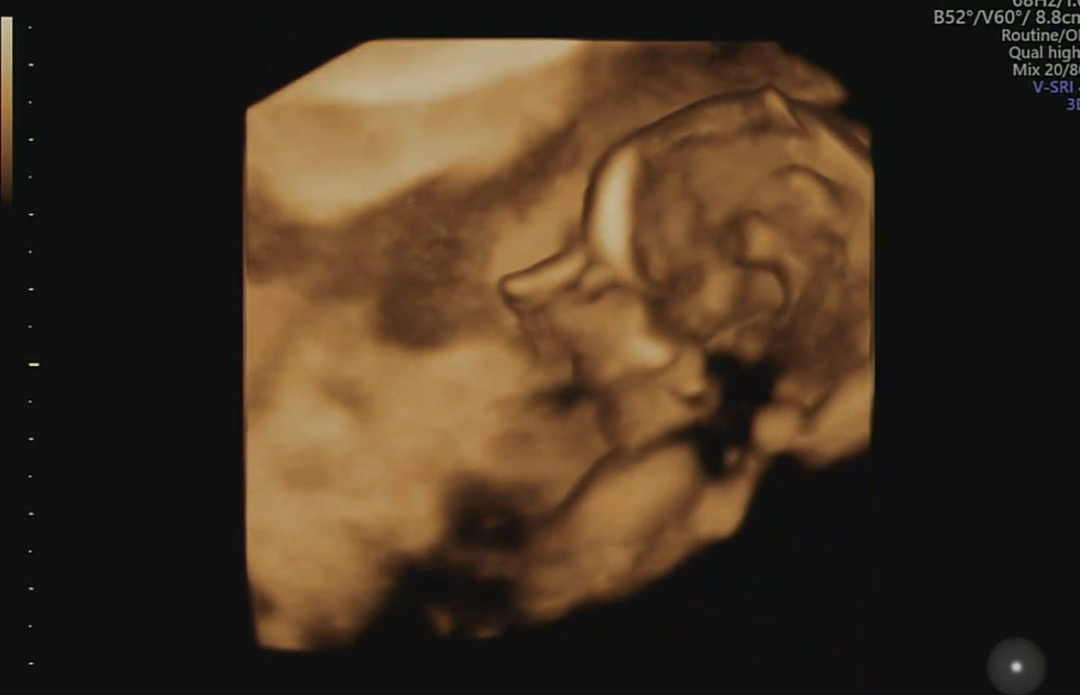

만 35세 둘째 맘 17주 입니다 다운 고위험 나와서 다음주 양수검사 앞두고 잇어요 ㅠㅠ 첫째때도 다운고위험이라 양수검사 햇엇는데 두번째라 괜찮을줄 알앗는데 아니엿네요 ㅠㅠㅠㅠ 12주 14주 아무리 촘파 봐도 콧대가 안보이고 원장님한테 이야기 해도 괜찮다고만 하셔셔 ㅠㅠㅠ 16주에 찍은 동영상 뒤져보니 잇더라구요 이정도면 걱정할 정도 아니겟죠 ㅠㅠ

콧대가 낮으면 다운증후군 확률이 높다해서 ㅠㅠㅠ 많이 걱정햇거든요 한시름 놓습니다 ㅠㅠ